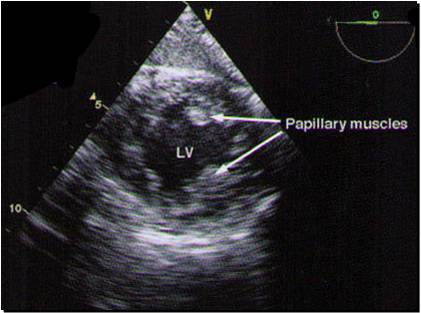

Here’s an easy 4 chamber view

A 2 chamber view